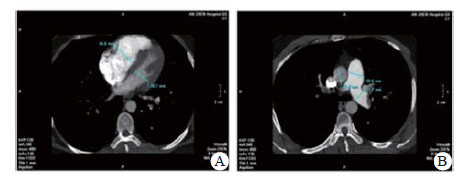

实验室检查结果:动脉血气分析pH 7.458, PaO2 60.5 mmHg, PaCO2 26.7 mmHg, SpO2 92.0%;D-二聚体2 655 ng/mL; BNP 163.00 pg/mL; 血常规WBC 5.91 ×1012/L, NE 73.8%, HGB 138.0 g/L, PLT 286 g/L; 同型半胱氨酸(HCY)14.0 μmol/L (正常值:6~14 μmol/L); 纤维蛋白原定量(FBG) 0.520 g/L(正常值:2.000~4.000 g/L), 纤溶酶原活性39.0%(73.0%~127.0%), 纤溶酶原抑制物-1(PAI-1)6.898 ng/mL(正常均数4.207 ng/mL), 组织纤溶酶原激活物(t-PA) 5.135 μg/L(正常均数2.375 μg/L); 血浆抗凝血酶Ⅲ(AT-Ⅲ:A)、血浆蛋白C活性(PC:a)、血浆蛋白S活性(PS:a)以及狼疮抗凝剂(Lupus anticoagulant, LA)水平在正常范围内。行经胸壁超声心动图检查提示右心扩大(因肺动脉瓣及三尖瓣反流极少, 无法准确估测肺动脉压力), 肺动脉增强CT(pulmonary artery computed tomography angiography, CTPA)提示右室扩大、两肺动脉主干及分支可见多发充盈缺损(图 2)。下肢静脉多普勒超声提示右侧腘静脉急性深静脉血栓形成及右侧股浅静脉血栓形成, 左侧髂静脉及左下肢深静脉未见明显异常。诊断为急性PE(高危组)、KTS。评估后给予重组组织型纤溶酶原激活物(r-tPA)50 mg 2 h内静脉泵入溶栓治疗, 溶栓过程中(r-tPA使用至35 mg时)患者出现咯血约200 mL, 遂被迫停止溶栓治疗, 监测活化凝血时间(accelerated clotting time, ACT)降至200s时给予普通肝素持续泵入并维持ACT于180~220 s, 肝素抗凝治疗48 h后改为低分子肝素(low molecular weight heparin, LMWH)联合华法林治疗, 期间未再发生咯血症状。入院第4天完善肺通气/灌注显像检查, 并提示:左肺下叶, 右肺中叶内段(亚段)、中叶外段、下叶前基底段、外基底段、后基底段血流灌注可见放射性分布稀疏缺损区, 双肺多发PE(累及8个肺段及1个亚肺段), 肺血流灌注受损范围占双肺容积的51%;入院10 d后复查CTPA, 结果显示两肺动脉主干腔内充盈缺损完全消失(图 3)。住院治疗15 d患者好转出院, 院外口服华法林抗凝治疗, 定期监测国际标准化比值(INR), 且维持于PE治疗范围2~3之间。抗凝治疗1年后进行肺通气/灌注显像复查, 提示右肺下叶前基底段、外基底段血流灌注改善, 左肺下叶, 右肺中叶内侧(亚段)、中叶外段、下叶后基底段血流灌注恢复正常。随访3年以来, 患者院外规律服用华法林抗凝治疗, 定期监测INR, 定期复查超声心动图及肺通气/灌注显像检查, 出院3个月超声心动图检查肺动脉压力正常、三尖瓣反流消失; 出院12个月及33个月复查肺通气/灌注未见新发的血流灌注稀疏缺损区, 出院33个月复查双髂双下肢静脉超声未见明显阻塞, 随访期间未出现出血或其他不良事件, 出院1个月后恢复工作至今, 一般状况良好。

| 图 2 患者CTPA(溶栓前):房室瓣水平显示右室明显扩张(A); 主肺动脉水平显示肺动脉增宽(B) |